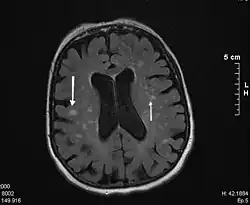

Común a los tres protocolos de diagnóstico se encuentra la característica clave de que debe encontrarse algún grado de deterioro cognitivo, acompañado de evidencia de alguna contribución de tipo vascular a dicho deterioro (que puede provenir de cualquier combinación entre historia clínica, examen físico, perfil cognitivo y evaluación diagnóstica, incluyendo neuroimagen).[cita requerida]

- Requerimiento de evidencia de patología cerebrovascular mediante neuroimagen.